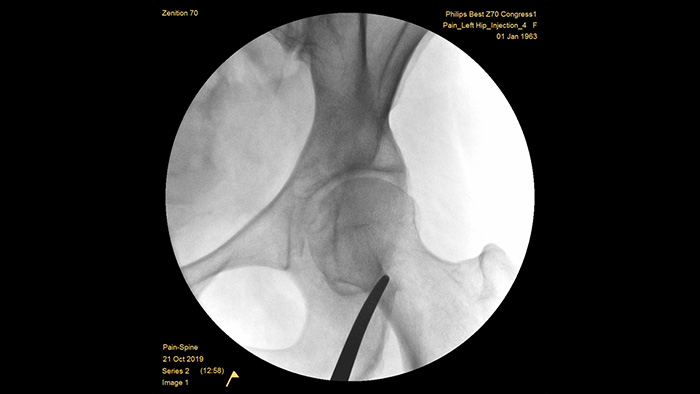

Philips ha logrado una reputación de excelencia en la adquisición de imágenes y la eficacia de la dosis durante más de medio siglo de experiencia en el desarrollo de sistemas de arco en C móviles para el entorno quirúrgico. Nuestras soluciones móviles de cirugía Zenition se basan en un planteamiento integral para la gestión de la dosis. Proporciona una calidad de imagen clínicamente relevante durante los procedimientos intervencionistas para las aplicaciones de tratamiento del dolor, a la vez que gestiona eficientemente la exposición a la radiación para los pacientes y el personal médico.

La preconfiguración única del examen de tratamiento del dolor permite a los usuarios configurar fácilmente el sistema durante los procedimientos intervencionistas para el tratamiento del dolor.

MetalSmart excluye automáticamente los artefactos metálicos causados por implantes metálicos para proporcionar una mayor calidad de imagen y un control de dosis eficiente para los procedimientos de tratamiento del dolor y para los pacientes con implantes metálicos, en comparación con los sistemas sin exclusión de metales. BodySmart promueve la adquisición de imágenes en el primer momento y la eficacia de la dosis al adaptar automáticamente el campo de medición al área de interés.

La profundidad óptima del arco en C perfectamente compensando proporciona amplitud de sala para ubicar a los pacientes obesos y obtener imágenes de la columna lumbar y la cadera. Admite la colocación sobre la mesa, incluso con mesas que tienen una base grande.